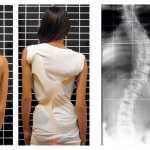

İnsan omurgasının anatomisi kafatasından başlayarak leğen kemiğine kadar uzanır. Arkadan tamamen bakıldığı zaman düz bir hat şeklindedir. Yandan bakıldığında boyun ve bel bölgesinde hafif çukurluklar bulunur..

Ancak sırt bölgesinde bulunan yüksek kamburluk kifoz olarak isimlendirilir. Oldukça yaygın olan bir rahatsızlıktır. Bu anlamda kamburluk tedavi seçenekleri de oldukça fazladır. Kamburluk tedavisine tamamen doktorlar karar vermelidir.